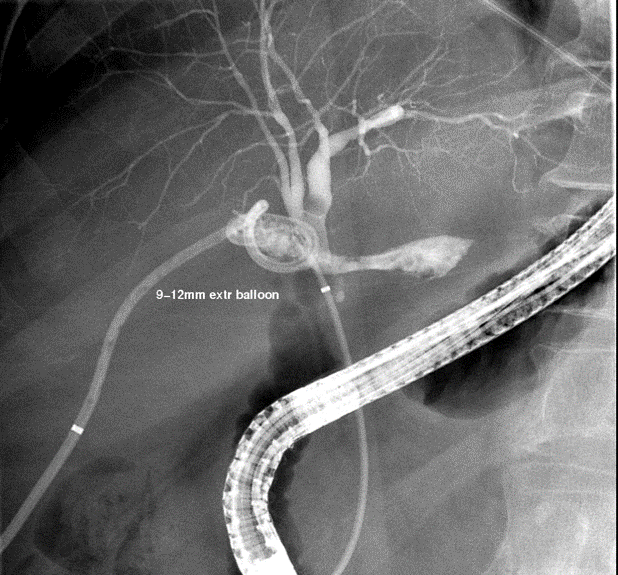

At this point, approximately two months after cholecystectomy, our hospital was asked for hepatobiliary (HPB) surgery and specialty interventional radiology consults. Given the anatomy, internalization of the PTBD was not possible and so stent exchanges were necessary when her tube became repetitively blocked. A tube check study two months postop, with contrast injected through the subhepatic percutaneous drain, interestingly showed back filling of non-dilated ducts in the posterior section (Figure 2).

Figure 2. Tube check study through a pigtail drain in the sub-hepatic space shows communication between a biloma in the gallbladder fossa and non-dilated posterior segment 6 and 7 biliary ducts.

Subsequent tube checks to visualize the size of the biloma demonstrated backfilling of the CBD through a newly patent cystic duct at 3 months post-operatively (see figure 3). A PTBD was inserted into the posterior sectional duct with its tip lying in the hilum and the subhepatic pigtail drain was removed from under the liver (see figure 4).

Figure 3. Tube check cholangiogram through percutaneous pigtail drain into biloma in the gallbladder fossa demonstrates new patency of the cystic duct (thick arrow) and back-filling of the CBD out of the biloma (thin arrow).